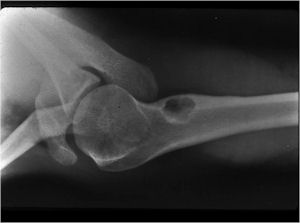

- Geographic, circumscribed lesion usually around 5cm in size.

- There may be expansion of bone, cortical thinning and cortical breakthrough. A soft tissue mass may accompany this lesion but the soft tissue component is usually contained by the periosteum.

- The periosteum remains intact around the soft tissue component. Might need a CT scan to detect the subtle calcification (Egg Shell Rim of Calcification) associated with an intact periosteal reaction

- The lesion may be entirely radiolucent but usually shows some degree of mineralization. Mineralization may appear stippled like cartilage but do not see chondroid pathologically. Mineralization is sometimes better detected on a CT scan rather than an x-ray.